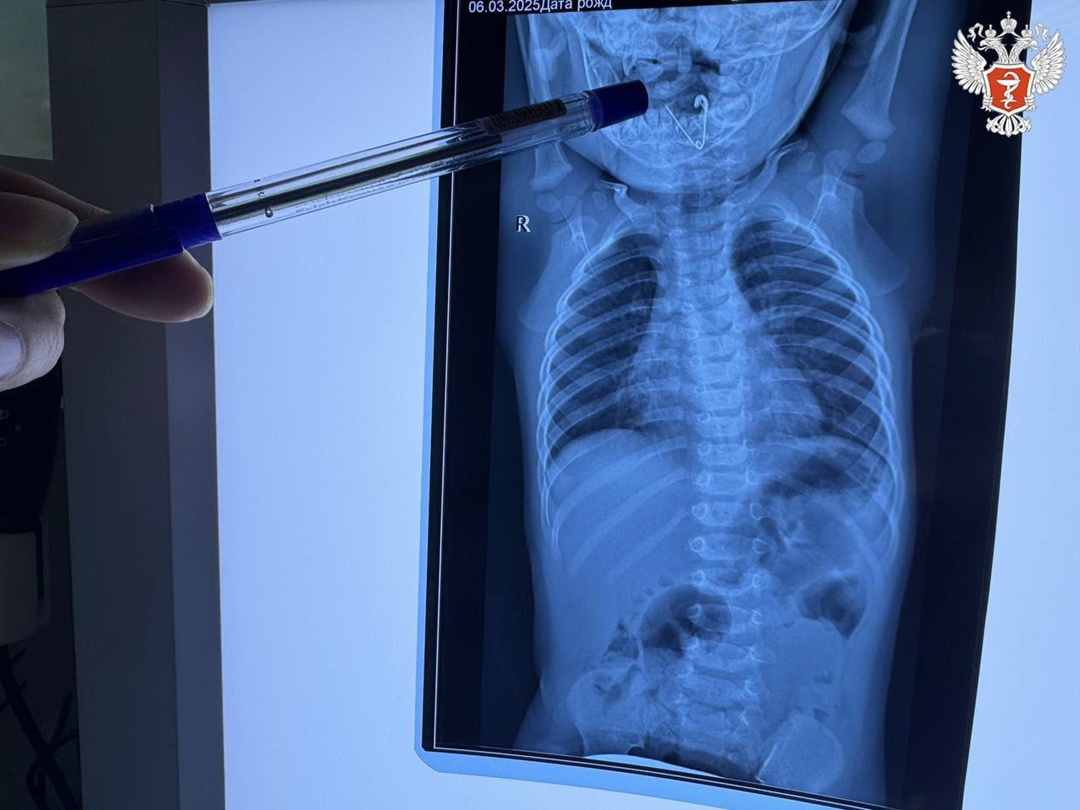

Бригада медиков госпитализировала маленького пациента в приемное отделение Черниговской центральной районной больницы. Специалисты выполнили обзорную рентгенографию органов грудной клетки и в пищеводе обнаружили тень инородного тела.

🩻 Малышу провели повторное рентгеновское исследование и на снимке увидели открытую булавку. Врачи удалили ее при помощи щипцов под контролем эндоскопической техники.